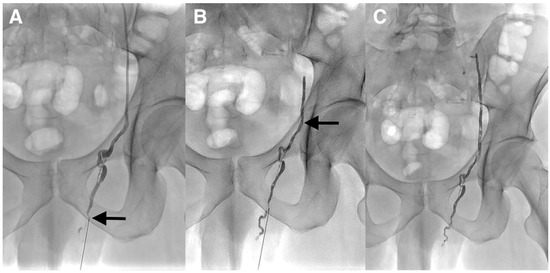

Figure 3. (A) The lack of visualization of the left testicular vein was felt to be due to its possible small caliber; therefore, the patient was scheduled for the antegrade embolization of the left testicular vein. The procedure was performed under local anesthesia. The testicular vein was percutaneously punctured with a 21-gauge metallic needle under ultrasound guidance at the left inguino-scrotal level by direct antegrade approach. A venogram through the needle was performed and demonstrated that the varicocele was supplied by the normal testicular vein (arrow). It was impossible to identify drainage into the left renal at the upper part on the venogram because of the risk of malposition of the needle during contrast injection. One explanation for the failure of the retrograde embolization was the competence of the first testicular vein valve at the level of the renal vein as often described despite the dilation of the testicular vein and the varicocele below. This valve could not be crossed. (B,C) Because of the inability to catheterize deeper the testicular vein with a microcatheter, cyanoacrylate glue embolization was directly performed through the 21-gauge needle. A mixture of Glubran®2 (GEM, Viareggio, Italy) and Lipiodol® (Guerbet, Aulnay-sous-Bois, France) in a 1:1 ratio was gently injected until the occlusion of the two-thirds of the testicular vein above the puncture site and few centimeters below this point (arrow). The catheter was removed and hemostasis was obtained with manual compression. The patient tolerated the procedure and was discharged the same day. He returned to his normal activity without pain and was asymptomatic at the 6 months follow-up. Varicoceles are often mainly treated with percutaneous embolization using fibered coils or sclerotherapy [1]. Coils have the advantage of being easy to use, especially detachable coils. The main drawbacks are the risk of migration if the size is not appropriate and the risk of recanalization, since small collaterals cannot be accurately treated with them. In addition, many coils may be necessary. The limitations of sclerotherapy are: the risk of migration/stroke, allergy, unpredictable diffusion space, total amount limited, inefficient in the case of large varicocele if used alone. The main advantage of sclerotherapy is the very low cost. Liquid embolic agents such as cyanoacrylates are less popular despite many advantages such as lower cost, faster procedure, and a higher capacity of the vein filling, especially collaterals [2]. A deep learning curve is necessary and the choice of low dilution with lipiodol is mandatory to avoid migration in the case of reflux. The entrapment of the microcatheter is exceptional in clinical practice if embolization is performed properly. There are not only a few cases with percutaneous antegrade varicocele embolization via the testicular vein at the level of the pubis, but also no reports of cyanoacrylate glue embolization in such a setting as we herein described [3,4].